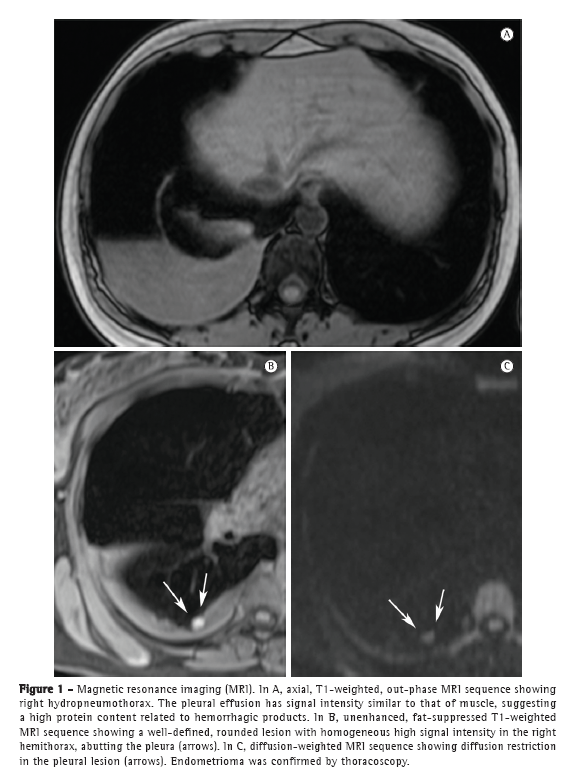

The patient underwent CT, which revealed right hydropneumothorax without focal lesions. On MRI scans of the chest, T1- and T2-weighted sequences showed right hydropneumothorax with hyperintense small nodular lesions (Figure 2), which are suggestive of endometriomas.

In recent years, MRI of the chest has progressed markedly. Because of improvements in speed and image quality, MRI is now ready for routine clinical use.(7-9) In both of the cases presented here, chest MRI revealed hydropneumothorax and well-defined, rounded nodules on the pleural surface in the right hemithorax. In Case 1, the pleural effusion had intermediate signal intensity on T1-weighted images, suggesting high protein content, probably related to hemorrhagic products. In Case 2, the pleural effusion had high signal intensity, suggesting recent hemothorax. The pleural nodules observed in Case 1 showed homogeneously high signal intensity on fat-suppressed T1-weighted images and restricted diffusion on diffusion-weighted imaging (DWI). In Case 2, the nodules showed heterogeneous signal intensity on T1- and T2-weighted images, without diffusion restriction. As in pelvic endometriosis,(1,10) pleural nodules of thoracic endometriosis might show different signal intensity on T1- and T2-weighted images, as well as variable diffusion restriction, depending on the age of the lesion.